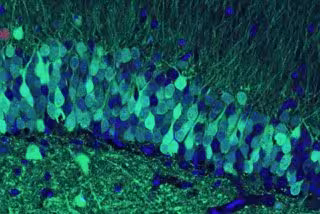

THE RAMIREZ GROUP, BOSTON UNIVERSITY - Archivo

Después, al identificar qué células formaban parte del proceso de creación de la memoria (lo que hicieron con la ayuda de una proteína verde brillante diseñada para iluminarse cuando se activan las células), fueron capaces de activar artificialmente esas memorias específicas de nuevo más tarde, utilizando la luz láser para activar las células de memoria.